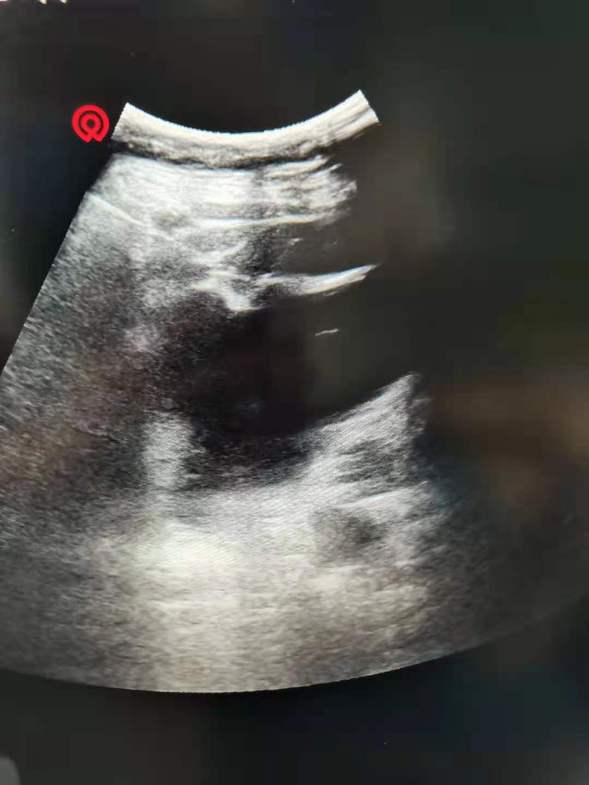

肾囊肿穿刺术中图像

对于身体条件差、麻醉风险大、不能够耐受手术的肾囊肿患者,可行经皮穿刺肾囊肿注入硬化剂治疗。该方法局麻下即可进行,安全性较高,必要时可重复穿刺。其可破坏囊壁的内皮细胞,使囊壁产生无菌性炎症,促使囊壁粘连和囊腔消失,从而达到去除囊肿对肾组织的压迫,即空间占位效应的目的。肾脏会随着呼吸小幅运动,射线类引导不能持续显示图像,不能让针尖停留在囊肿中心,超声引导定位精准,穿刺容易,实时显示,能小幅实时微调,能有效避免意外损作,减少并发症的发生概率。硬化剂,可破坏囊壁的内皮细胞,使内皮组织变性萎缩,然后纤维化。其刺激性小,止痛效果好,而且不需反复。